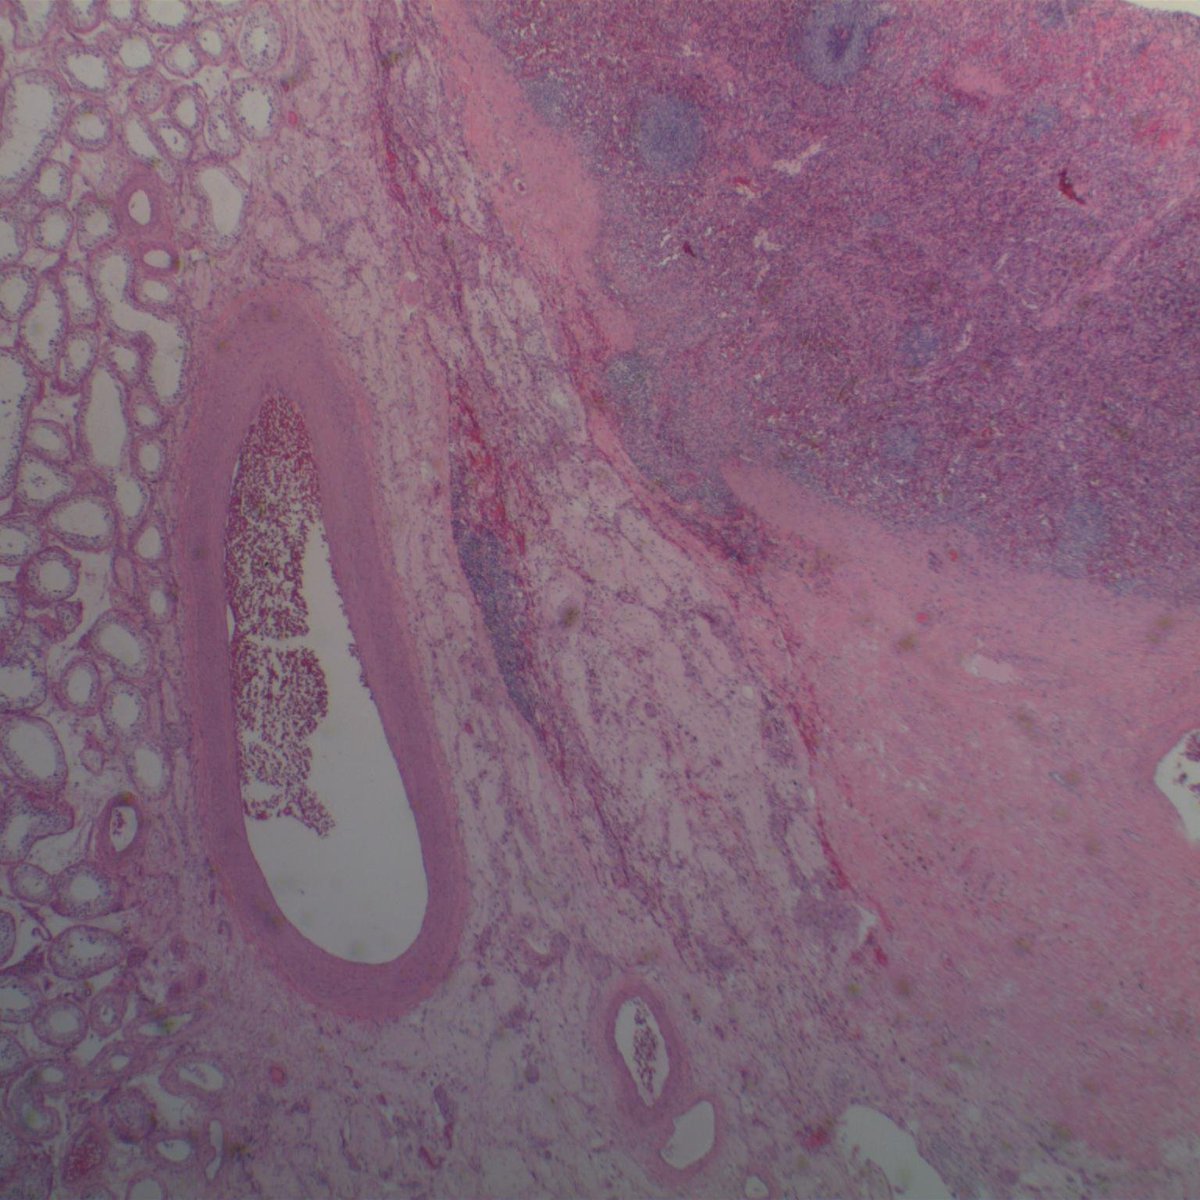

May is #bladdercancerawarenessmonth - important to recognize lesions which mimic #bladdercancer Nephrogenic metaplasia/adenoma: - various architectures (papillary, tubular/glandular, vascular-like...) - cuboidal to hobnail nuclear features - prominence of basement membrane